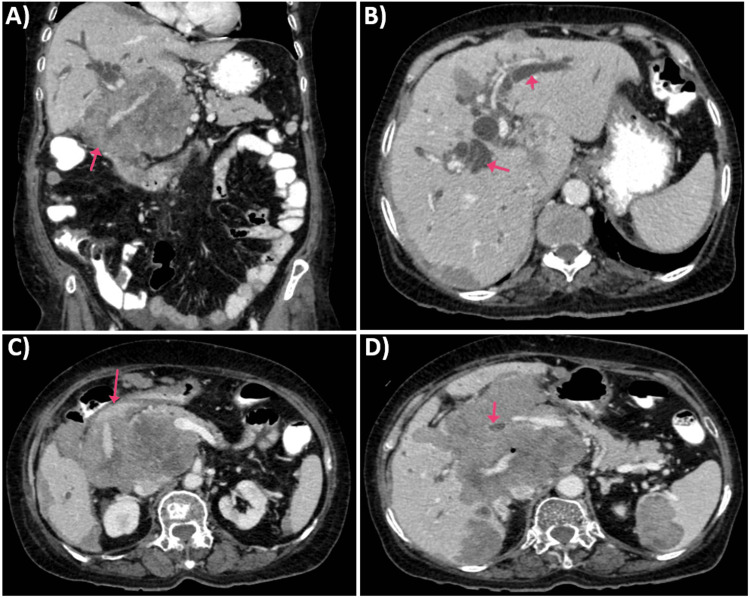

Imaging studies, including ultrasound and CT scan, identified a mass in the caudate lobe of the liver with dilated intrahepatic bile ducts (Figures 1A, 1B), encroaching on the duodenum (Figure 1C), and CBD (Figure 1D), causing partial gastric outlet obstruction and obstructive jaundice. PET-CT (Figure 2) confirmed persistent abnormally increased fluorodeoxyglucose (FDG) uptake in a hypo-enhancing lesion at the post-operative site in the caudate region, infiltrating the first and second parts of the duodenum with luminal narrowing and showing effacement of fat planes with the portal vein and inferior vena cava (IVC). The lesion also abutted the head of the pancreas with suspicious loss of the fat plane, measuring approximately 66 x 68 mm (SUVmax 14.8). Persistent abnormally increased FDG uptake was also noted in a hypo-enhancing lesion involving the splenic parenchyma adjacent to the hilum, measuring 28 x 20 mm (SUVmax 4.2). Upper GI endoscopy with side view scope (esophagogastroduodenoscopy (EGD)) revealed external compression on the duodenum with D1 mucosa edematous, erythematous with superficial ulceration causing D1 and D2 narrowing, corroborating the imaging findings of partial gastric outlet obstruction (Figure 3).